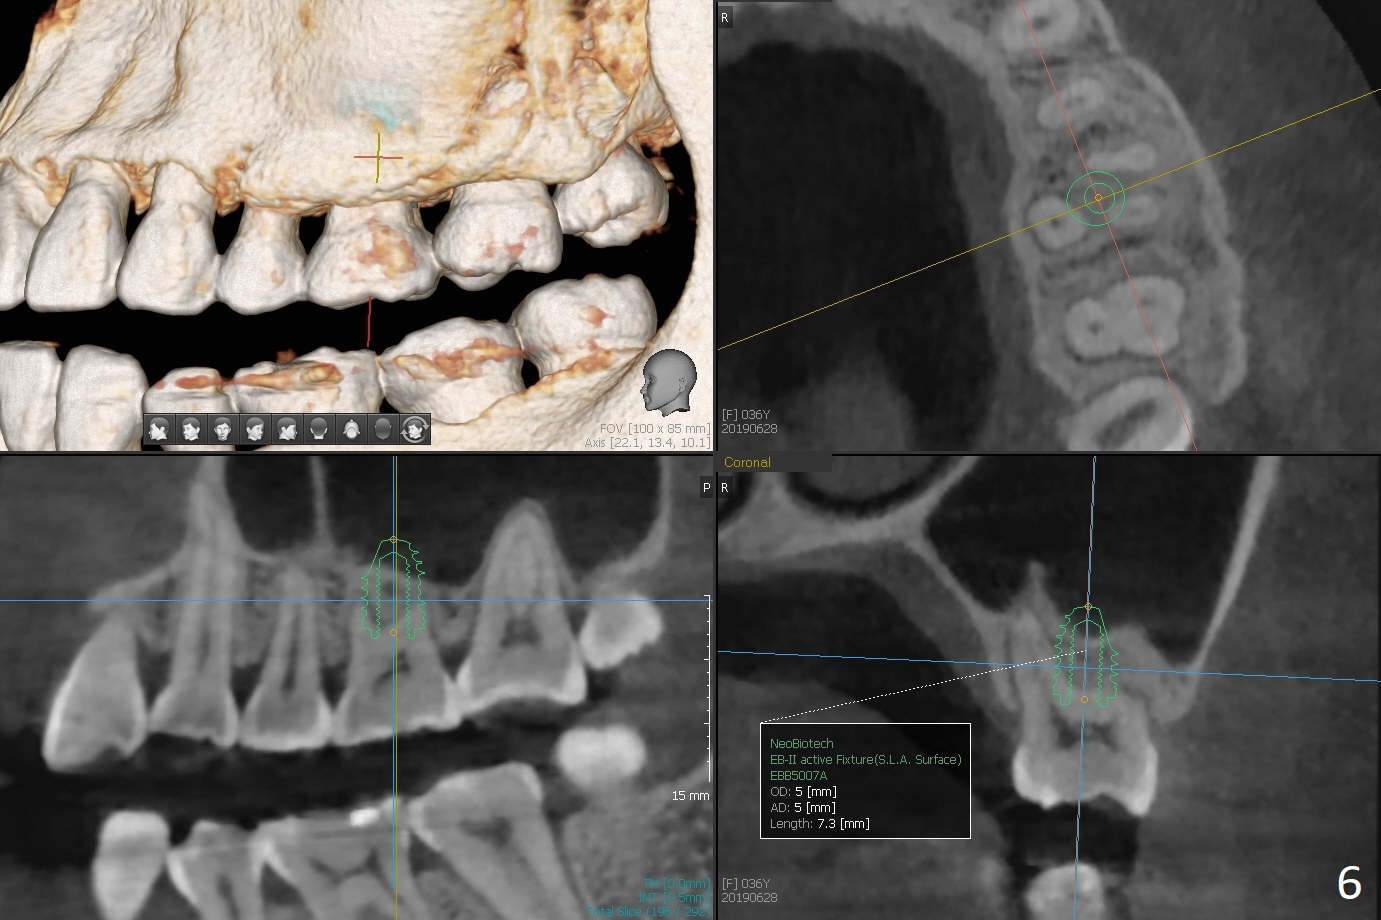

A 36-year-old woman is nervous about dentistry. She will take Valium by herselft before surgery (Fig.1). The tooth #3 has 3 residual roots (Fig.2 (CBCT 3 D occlusal view)). The bone is 2-3 mm thick (Fig.3,4 (sagittal, coronal sections)). A 5x7.3 mm implant will be placed with IS guide (Fig.5 (12 mm offset)). Since IBS implants are able to achieve amazing stability in the thin bone, prepare the shortest 4-5 mm in diameter dummy implants (IS (better surface treatment) and IBS) after sinus lift using UF Guided Sinus Lift Approach Kit (surgery). With intact tooth structure at #14, the bone height is not much (Fig.6), congenital (genetic) in nature. The infection at #31 is more severe (Fig.7). Extraction will be the 2nd in order. Because of limited bone, it is better to do bone graft first. The patient is concerned about the discolored upper right canine, which should be associated with orthodontics 20 years ago (take photos). The apical canal is obliterated (Fig.8,9 arrow) with periapical radiolucency (arrowhead). In fact the bone at #31 is so little that the tooth will be extracted for socket preservation.